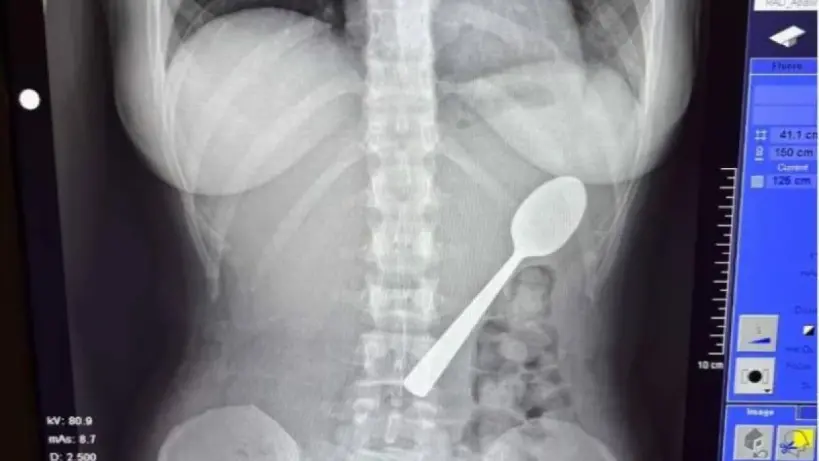

في حادثة غريبة أثارت دهشة الكثيرين، اضطرت بلجيكية تبلغ من العمر 28 عاماً للخضوع لعملية طبية بسيطة لإخراج ملعقة ابتلعتها عن طريق الخطأ، الحادثة وقعت عندما كانت ريمي أميلينكس جالسة على الأريكة في منزلها لتناول الزبادي، قبل أن يقفز عليها بشكل مفاجئ كلبها مارلي.

أثناء محاولة الكتابة على هاتفها، كانت الملعقة في فمها، وفي لحظة غير متوقعة، وجدتها عالقة في حلقها بعد دفع الكلب لها دون قصد، ورغم محاولاتها لإزالتها بيدها، إلا أن الملعقة انزلقت إلى معدتها.

توجهت ريمي إلى غرفة الطوارئ، حيث طمأنها الأطباء ونصحوها بالانتظار حتى يُحدد موعد لتنظير المعدة، وفي الليلة نفسها، عانت من الشعور بالانتفاخ والغثيان، وصعوبة في تناول الطعام والنوم بسبب وجود الملعقة.

بعد مرور يومين، تمكن الاطباء من إزالة الملعقة بتخدير موضعي، على الرغم من أن العملية تسببت في نزيف بسيط، فإن ريمي شعرت بارتياح كبير وعادت الي حياتها اليومية بسرعة، اطلق عليها زملاؤها في العمل لقب "الفتاة ذات الملعقة".